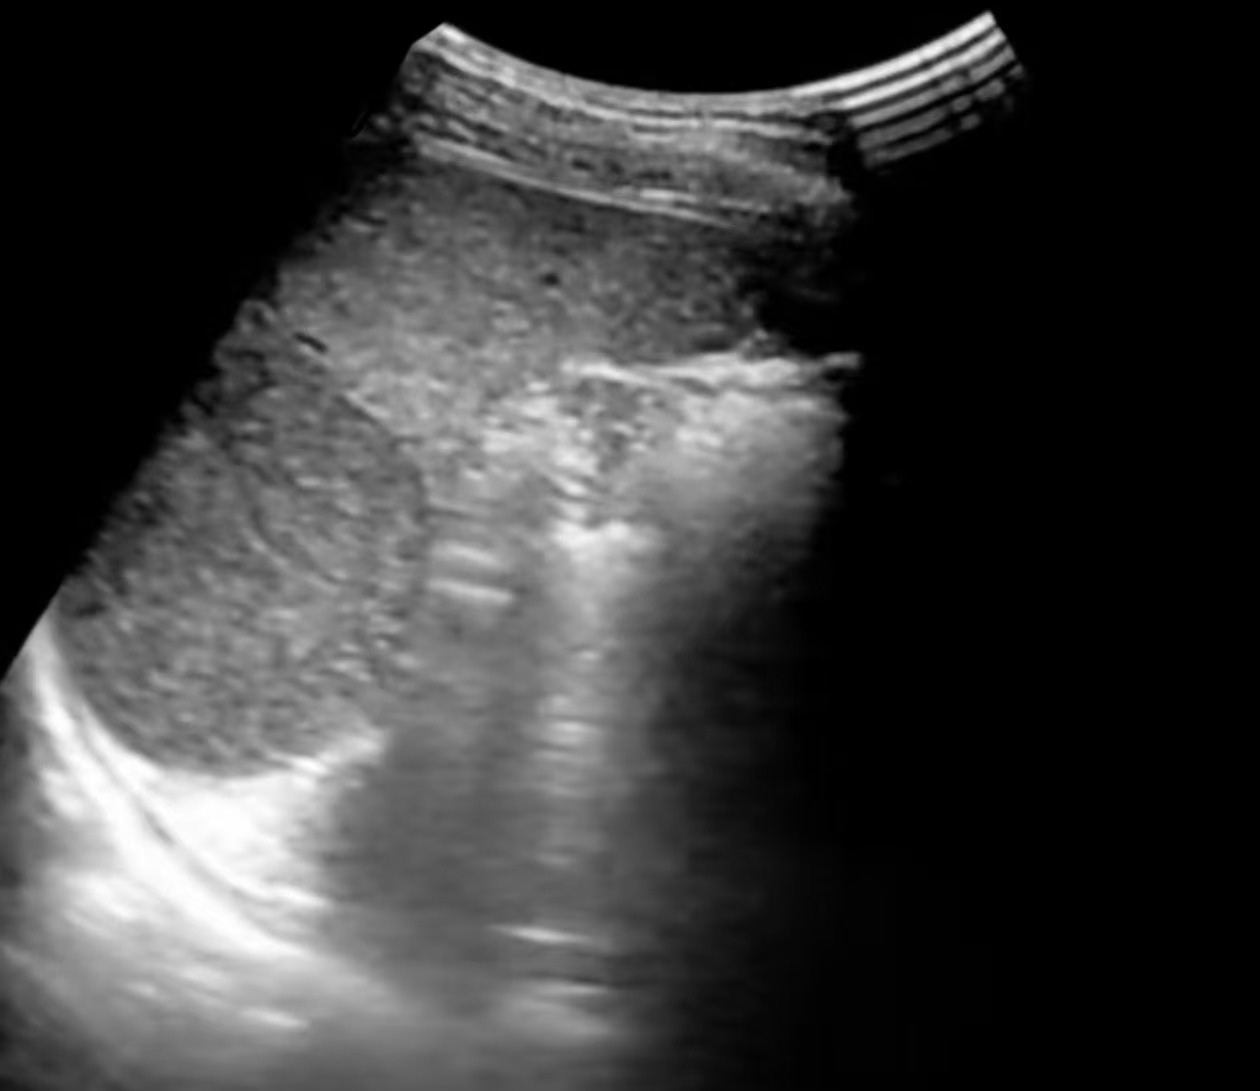

脾血管瘤的“超声肖像”:

常见类型与表现

脾血管瘤在超声下的“长相”并非千篇一律,主要可分为三种经典类型,超声医生正是通过这些特征来进行判断:

• 超声描述:脾实质内出现一个或多个边界清晰的明亮团块(回声高于周围正常的脾组织),像夜空中的星星。

• 内部特征:内部回声均匀或呈细网格状,后方回声无明显变化或略有增强。

• 血流信号:彩色多普勒超声下,多数未见明显血流信号或仅见周边点状血流。这是因为血管瘤内血流速度极其缓慢。

• 这是最典型、最经典的脾血管瘤表现,诊断信心较高。